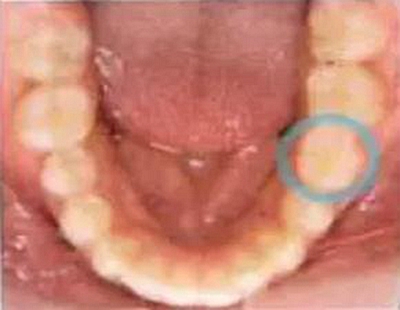

病例②怎么辦?。?!上下頜錯位

“咀嚼時孩子的上下頜會有錯位。”

一下子咬合的話下頜向左錯位。

臉也看上去有點左右不對稱。